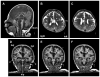

TARP syndrome, comprising Talipes equinovarus, atrial septal defect (ASD), Robin sequence (micrognathia, glossoptosis, and cleft palate), and persistence of the left superior vena cava, is an X-linked condition with pre- or postnatal lethality in affected males. Based on linkage studies and massively parallel sequencing of X-chromosome exons in two families, the disease-causing gene was identified as RBM10. We identified a maternally inherited frameshift mutation in an unrelated patient, confirming RBM10 as the disease gene. This is the first reported individual with TARP syndrome who survived past early infancy, thus expanding the phenotypic spectrum of this disorder. In addition to the characteristic cleft palate, ASD, and persistent superior vena cava, he had low-set and posteriorly angulated ears, upslanting palpebral fissures, cryptorchidism, and structural brain abnormalities including partial agenesis of the corpus callosum, dysplastic enlarged caudate, and cerebellar hypoplasia with megacisterna magna. Preterm delivery, suspected pulmonary hypoplasia, and pulmonary hypertension resulted in chronic lung disease. At the age of 3(7)/(12) years, he remained ventilator-dependent at night, and he was fed exclusively through a gastro-jejunal tube. Sensorineural hearing loss required a hearing aid. Optic atrophy and cortical visual impairment were noted. He was unable to sit independently, was non-communicative and he had severe intellectual disability. Atrial flutter required recurrent ablation of intra-atrial re-entry pathways. The mother's heterozygosity for the RBM10 mutation underscored the importance of accurate diagnosis and counseling for TARP syndrome.